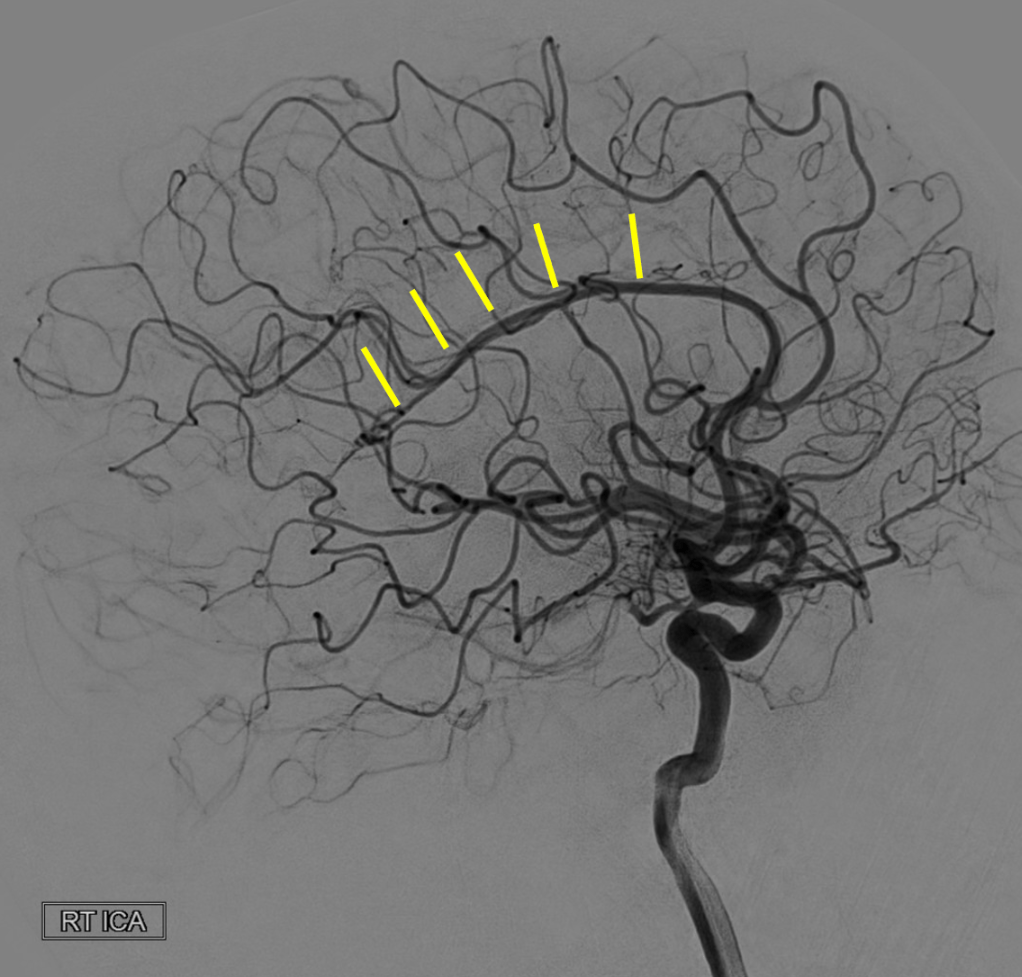

On this lateral view R ICA injection, name these two branches:

Pericallosal and callosomarginal arteries off the ACA